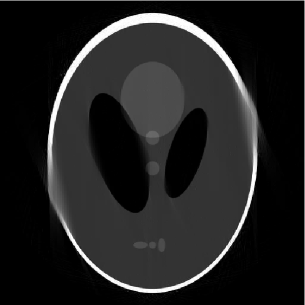

Figure 2: (a) 155155155 limited-angle projections in the 2-D frequency plane, (b) the full and outer-shell masks of the Shepp-Logan phantom, (c) FBP (PSNR=19.9PSNR19.9\mbox{PSNR}=19.9 dB), (d) DORE (PSNR=22.7PSNR22.7\mbox{PSNR}=22.7 dB), (e) GPSR (PSNR=22.9PSNR22.9\mbox{PSNR}=22.9 dB), (f) FPCASAS{}_{\footnotesize\mbox{AS}} (PSNR=22.5PSNR22.5\mbox{PSNR}=22.5 dB), (g) mask DORE (PSNR=25.8PSNR25.8\mbox{PSNR}=25.8 dB), (h) mask GPSR (PSNR=25.3PSNR25.3\mbox{PSNR}=25.3 dB), and (i) mask FPCASAS{}_{\footnotesize\mbox{AS}} (PSNR=26.4PSNR26.4\mbox{PSNR}=26.4 dB) reconstructions.

Shepp-Logan phantom reconstruction. We simulated limited-angle parallel-beam projections of an analog Shepp-Logan phantom with 1superscript11^{\circ} spacing between projections and missing angle span of 25superscript2525^{\circ}. Each projection is computed from its analytical sinogram using [8, function ellipse_sino.m] and [7] and then sampled by a receiver array containing 511511511 elements. We then compute FFT of each projection, yielding N=512𝑁512N=512 frequency-domain measurements; the corresponding frequency-domain sampling pattern is shown in Fig. 2.

Fig. 2 depicts both the full and outer-shell masks of the phantom that we use to implement the DORE, GPSR, FPCASAS{}_{\footnotesize\mbox{AS}} and mask DORE, GPSR, and FPCASAS{}_{\footnotesize\mbox{AS}} methods, respectively. Because of the nature of X-ray CT measurements, our full mask has circular shape containing p=205859𝑝205859p=205859 signal elements. The elliptical outer-shell mask containing pM=1308150.6355psubscript𝑝M1308150.6355𝑝p_{{\scriptstyle{\rm M}}}=130815\approx 0.6355\,p pixels has been constructed from the phantom’s sinogram using k=1180Aπ(k1)/180superscriptsubscript𝑘1180subscript𝐴𝜋𝑘1180\bigcap_{k=1}^{180}A_{\pi\,(k-1)/180}, see Section V; this choice of the mask implies that we have prior information about the shape of the outer shell of the Shepp-Logan phantom beyond the information available from the limited-angle projections that we use for reconstruction, see Fig. 2.

Figs. 22 show the reconstructions of various methods. To facilitate comparison, we employ the common gray scale to represent the pixel values within the images in Figs. 22. Clearly, taking the object’s contour into account improves the signal reconstruction performance.